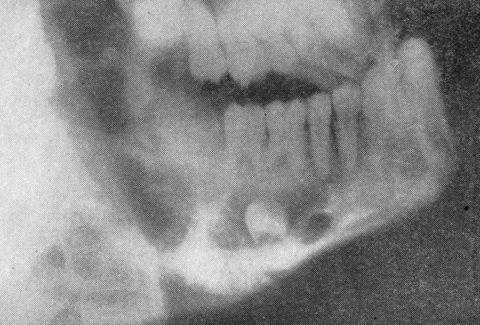

Рентгенографически при начальных стадиях рака верхней челюсти, развивающегося со слизистой оболочки гайморового синуса, выявляют завуалированность пазухи. В участке шва, соединяющего альвеолярный отросток со скуловой костью, а также в области нижнеглазничной щели обнаруживают деструктивные изменения кости, нехарактерные для хронического гайморита. На прицельной рентгенограмме определяют резорбцию костной ткани в зоне межзубных и межкорневых перегородок. На поздних стадиях резорбтивные процессы протекают по типу «тающего сахара» без признаков регенерации кости.

На R-граммах нижней челюсти - деструкция более одной анатомической части нижней челюсти с наличием патологического перелома.

Ключевым способом исследования пациентов с остеосаркомой является рентгенография. На рентгенологических снимках врач определяет отдельные участки растворения кости или замещения ее соединительной тканью.